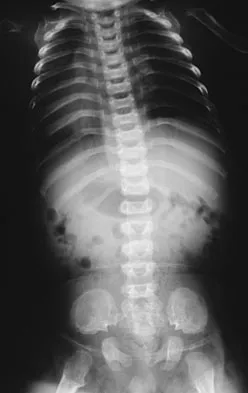

A 2-year-old boy has complete absence of the sacrum and lower lumbar spine. What is the most likely long-term outcome if no spinal pelvic stabilization is performed?

Explanation

Without stabilization, progressive kyphosis will develop between the spine and pelvis. The kyphosis progresses to the point that the child must use his or her hands to support the trunk, and therefore is unable to use his or her hands for other activities. Neck extension contracture does not usually develop. Neurologic deficit, including sexual dysfunction, is generally present at birth and static. Tachdjian MO: The spine: Congenital absence of the sacrum and lumbosacral vertebrae (lumbosacral agenesis), in Wickland EH Jr (ed): Pediatric Orthopaedics, ed 2. Philadelphia, PA, WB Saunders, 1990, vol 3, p 2228.